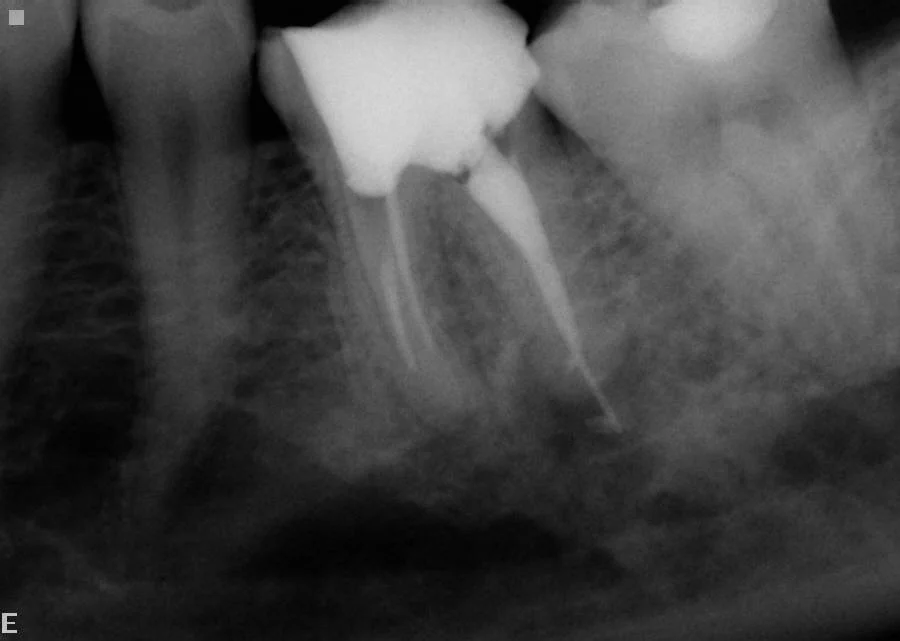

The nerve on this tooth had died causing infection and bone loss around the roots. Options were root treatment (endodontics) or extraction.

After treatment, showing good root filling of three roots. The tooth is still functional and symptomless after one year.